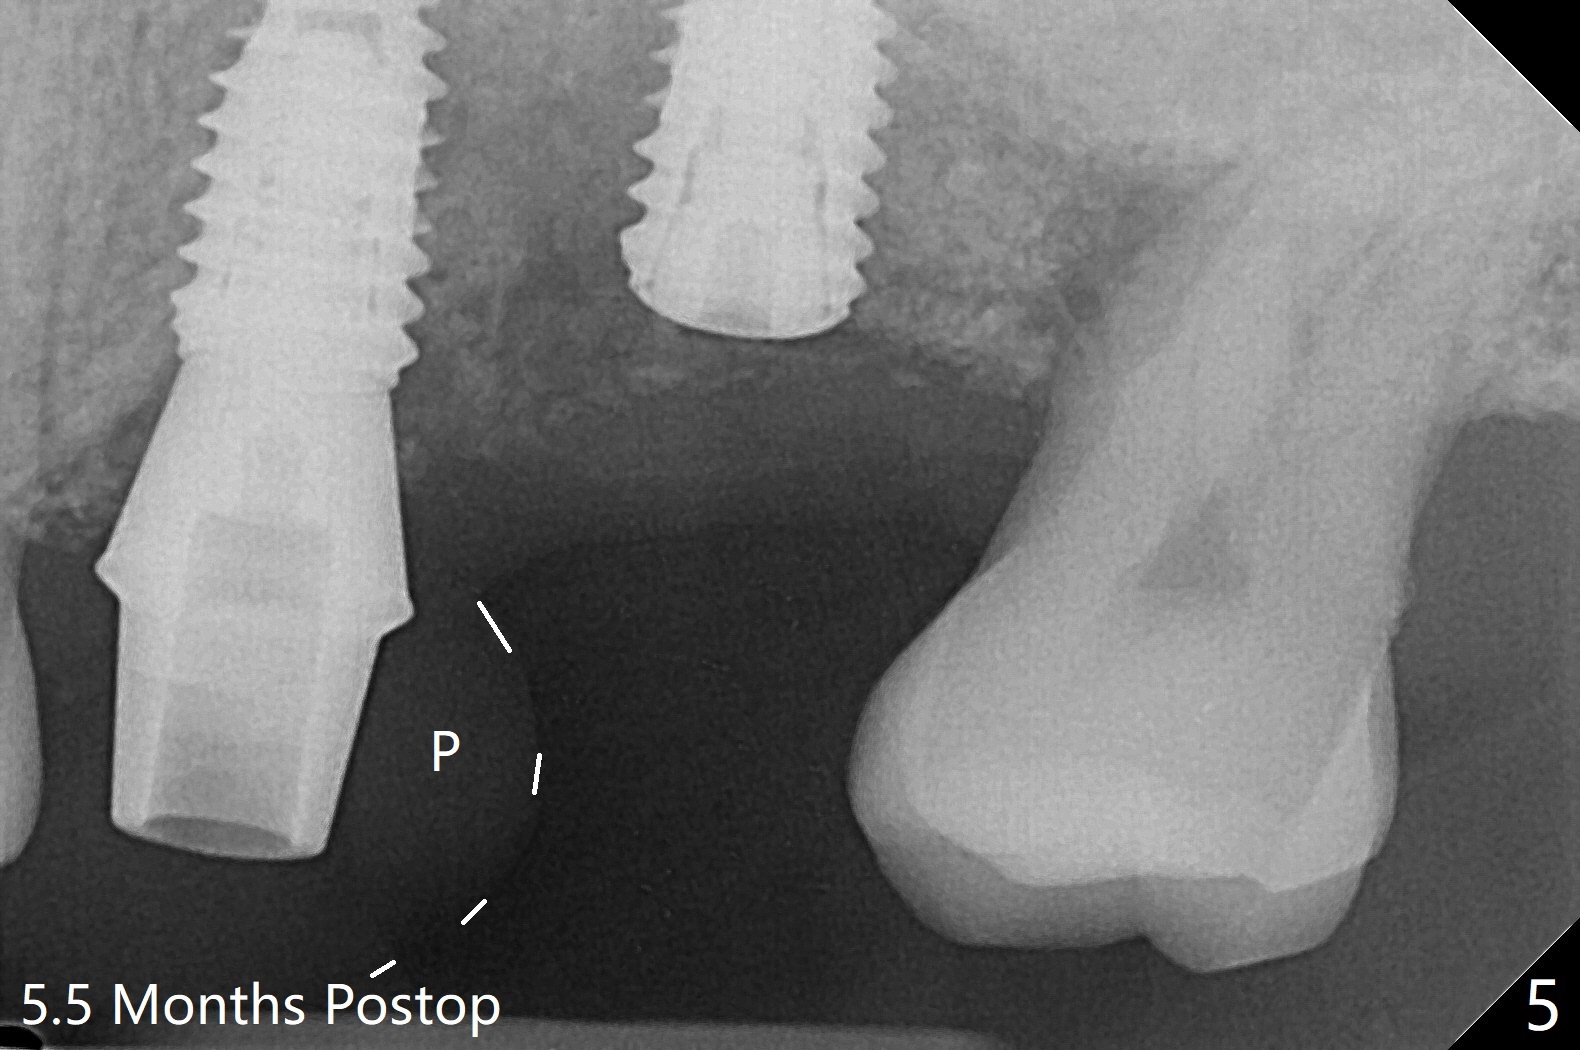

左上六植牙第三次失败后五个月,牙槽嵴宽度尚可,切开后放置导板,3.2乘19毫米园钻头好像接近上颌窦底板(图一),但是粘性骨块和4乘10毫米报废植体就不能进入上颌窦(图二),最后不得不使用3毫米Bicon骨凿,之后同一个报废植体就似乎进入上颌窦(图三),4.5乘8.5毫米正式植体植入深度和稳定性均正常(图四),腭侧植体稍微暴露,放置愈合螺丝后,放置骨粉和PRF膜,缝合,左上5植体放置5.7x4.5(4)毫米基台,固定牙周敷料。术后5.5个月植体好像整合(图五),缺牙间隙特别小,5临时牙冠(P)必须取出才能切开暴露植体,放置5.5x5毫米愈合基台(图六)。伤口愈合后,必须做渐进性负荷,之后做简单局部矫正,推7往远中,6缺失3年,7往近中倾斜移位。两周后牙周敷料脱落,伤口愈合,放置修复基台,故意将基台平面朝远中,足够空间制作临时牙冠(图七)。调整基台长度(比较图七,八)。制作连体牙冠(5,6),有意提高5牙冠高度,使左上7不与对合牙接触,有利于远中移位(图九)。也要在对侧提高咬合(图十)。局部矫正一个月后,磨去右侧咬合垫和磨短左上5,6临时牙冠,前牙还不能完全接触(图十一)。1-2星期前牙开合自行消失,取模做左上5,6牙冠。局部矫正似乎使左上7远中移位大约3毫米(比较图十二,十三)。粘固拧紧后(20 Ncm)14号牙牙冠咬合增高,拍摄根尖片(图十三),两个基台好像仍然完全就位,然后调整咬合。